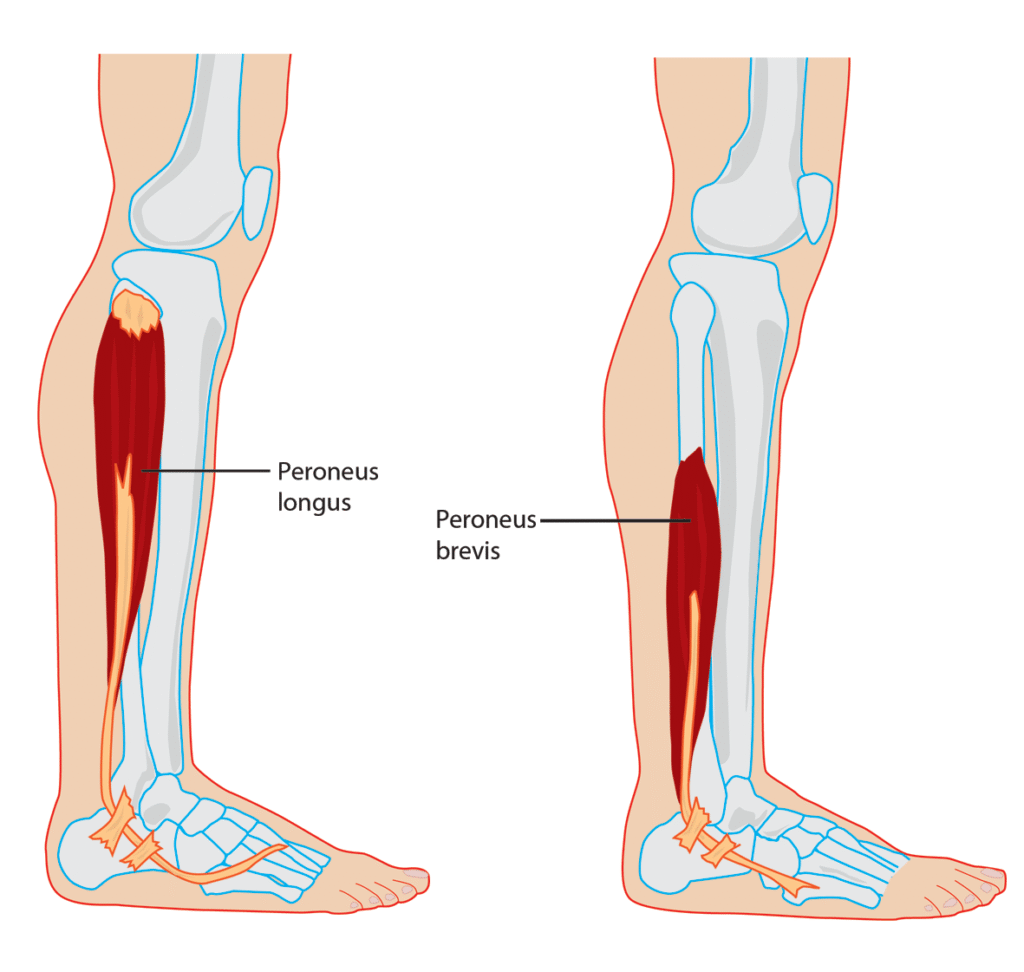

Peroneal retinaculum

- Smärta i fotled, plantarfascit, peroneus-överbelastning

- Instabilitet i fotleden och ibland smärta vid fibulaspetsen

En lateral tibiakondylfraktur kan indirekt påverka både fibula och foten, särskilt genom biomekaniska förändringar, felställningar och belastningsförskjutningar. Fibula är inte direkt involverad i frakturen, men kan påverkas sekundärt.

- Ligamentskador: Fibula är fästpunkt för laterala ligament (t.ex. LCL), som kan skadas vid frakturen.

🦶 Möjlig påverkan på foten

- Neurologisk påverkan: Om nervstrukturer (t.ex. n. peroneus) påverkas vid frakturen, kan det ge nedsatt funktion i foten.